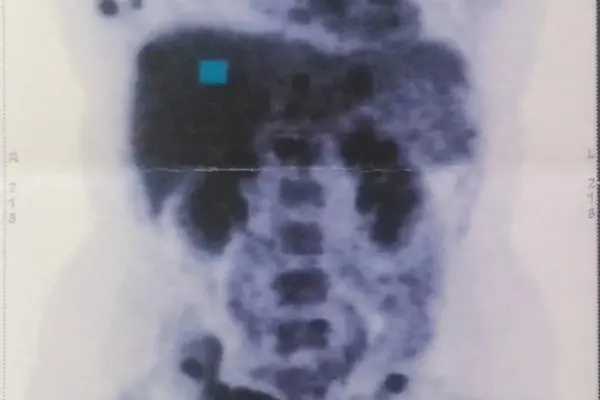

Sedíme a čekáme... v hlavě mi projíždí, že jsem tu nejmladší a proč zrovna já. Tahle otázka mě provázela poměrně dlouhou dobu. Volají mě, jdeme do ordinace... už v prvních vteřinách jsem věděla, že moje rozhodnutí bylo správné. Paní profesorka je úžasná. Vysvětlila mi, jaký typ nádoru mám, jak se léčí, odpověděla na každou otázku a poslala na pár dalších vyšetření, abychom věděly naprosto vše. Nejdůležitější bylo PET/CT a genetika.

Na PET/CT neboli petko, jsem šla za pár dní, i když čekačka je za normálních okolností týdny. Výsledky byly poměrně rychle, a tak už jsem zase seděla v čekárně. Zavolání, příchod, židle, pár slov a zastavil se čas. „Bohužel máte metastáze v uzlinách, játrech a v kostech, hlavně v pánvi, rukou, lopatkách, páteři...“ CO TEĎ?! Smířená s rakovinou jsem byla, ale ne v takovém rozsahu. Nikdo nechápal a do dnešního dne nechápe, jak je to v mém věku možné.